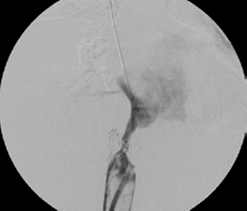

Se procedió a realizar angioplastias secuenciales con balones de 10, 12 y 14 mm de diámetro (Boston Sci. Corp.), logrando repermeabilizar la vena cava, pero con una estenosis residual del 60 % (figura 5). Se continuó colocando dos endoprótesis (stents) de Palmaz con balón montado de 24 mm de diámetro (Cordis™ - Johnson & Johnson). La vena cava se recanalizó de manera completa y las venas suprahepáticas eran permeables (figura 6).